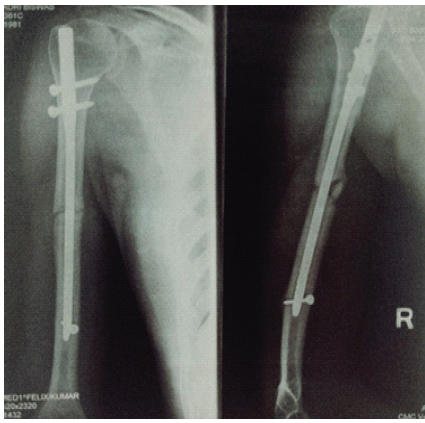

A 44-year-old male patient presented to our hospital with complaints of moderate pain and functional limitation of the operated upper limb for 4 months. He had a significant history of a right humeral shaft fracture sustained in February 2005 following a road traffic accident. At that time, he underwent surgical fixation at his hometown hospital, reportedly by closed reduction and internal fixation using an IMIL nail for the humerus on February 08, 2005. The post-operative period was uneventful, and he remained asymptomatic for many years (Fig. 1).

Figure 1: Post-operative anteroposterior and lateral radiographs showing intramedullary interlocking nailing of the right humerus performed in February 2005.